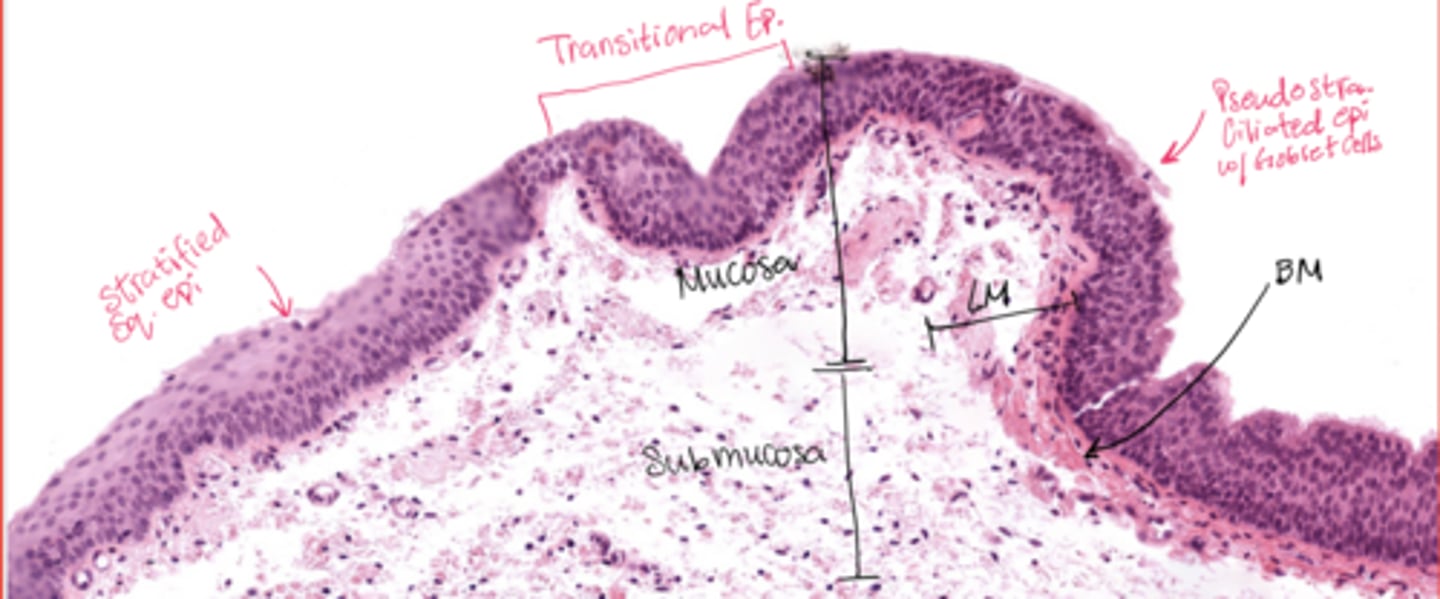

What epithelial transition occurs in the larynx?

Pseudostratified ciliated epithelium -> stratified squamous epithelium (image is at the vestibular folds)

Understand how the epithelium changes from epiglottis to treachea`

Epiglottis - stratified squamous epithelium with elastic cartilage

False vocal cords - pseudostra. cillated epithelium

True vocal cords - stratified sq. non keratinized epithelium with skeletal muscle

Trachea - pseudostra. ciliated epithelium with goblet cells (respiratory structure)

Describe the transitional epithelium of the larynx

The main transition occurs near the vocal cords, separating the squamous epithelium of the true vocal cords from the respiratory epithelium pseudostratified ciliated